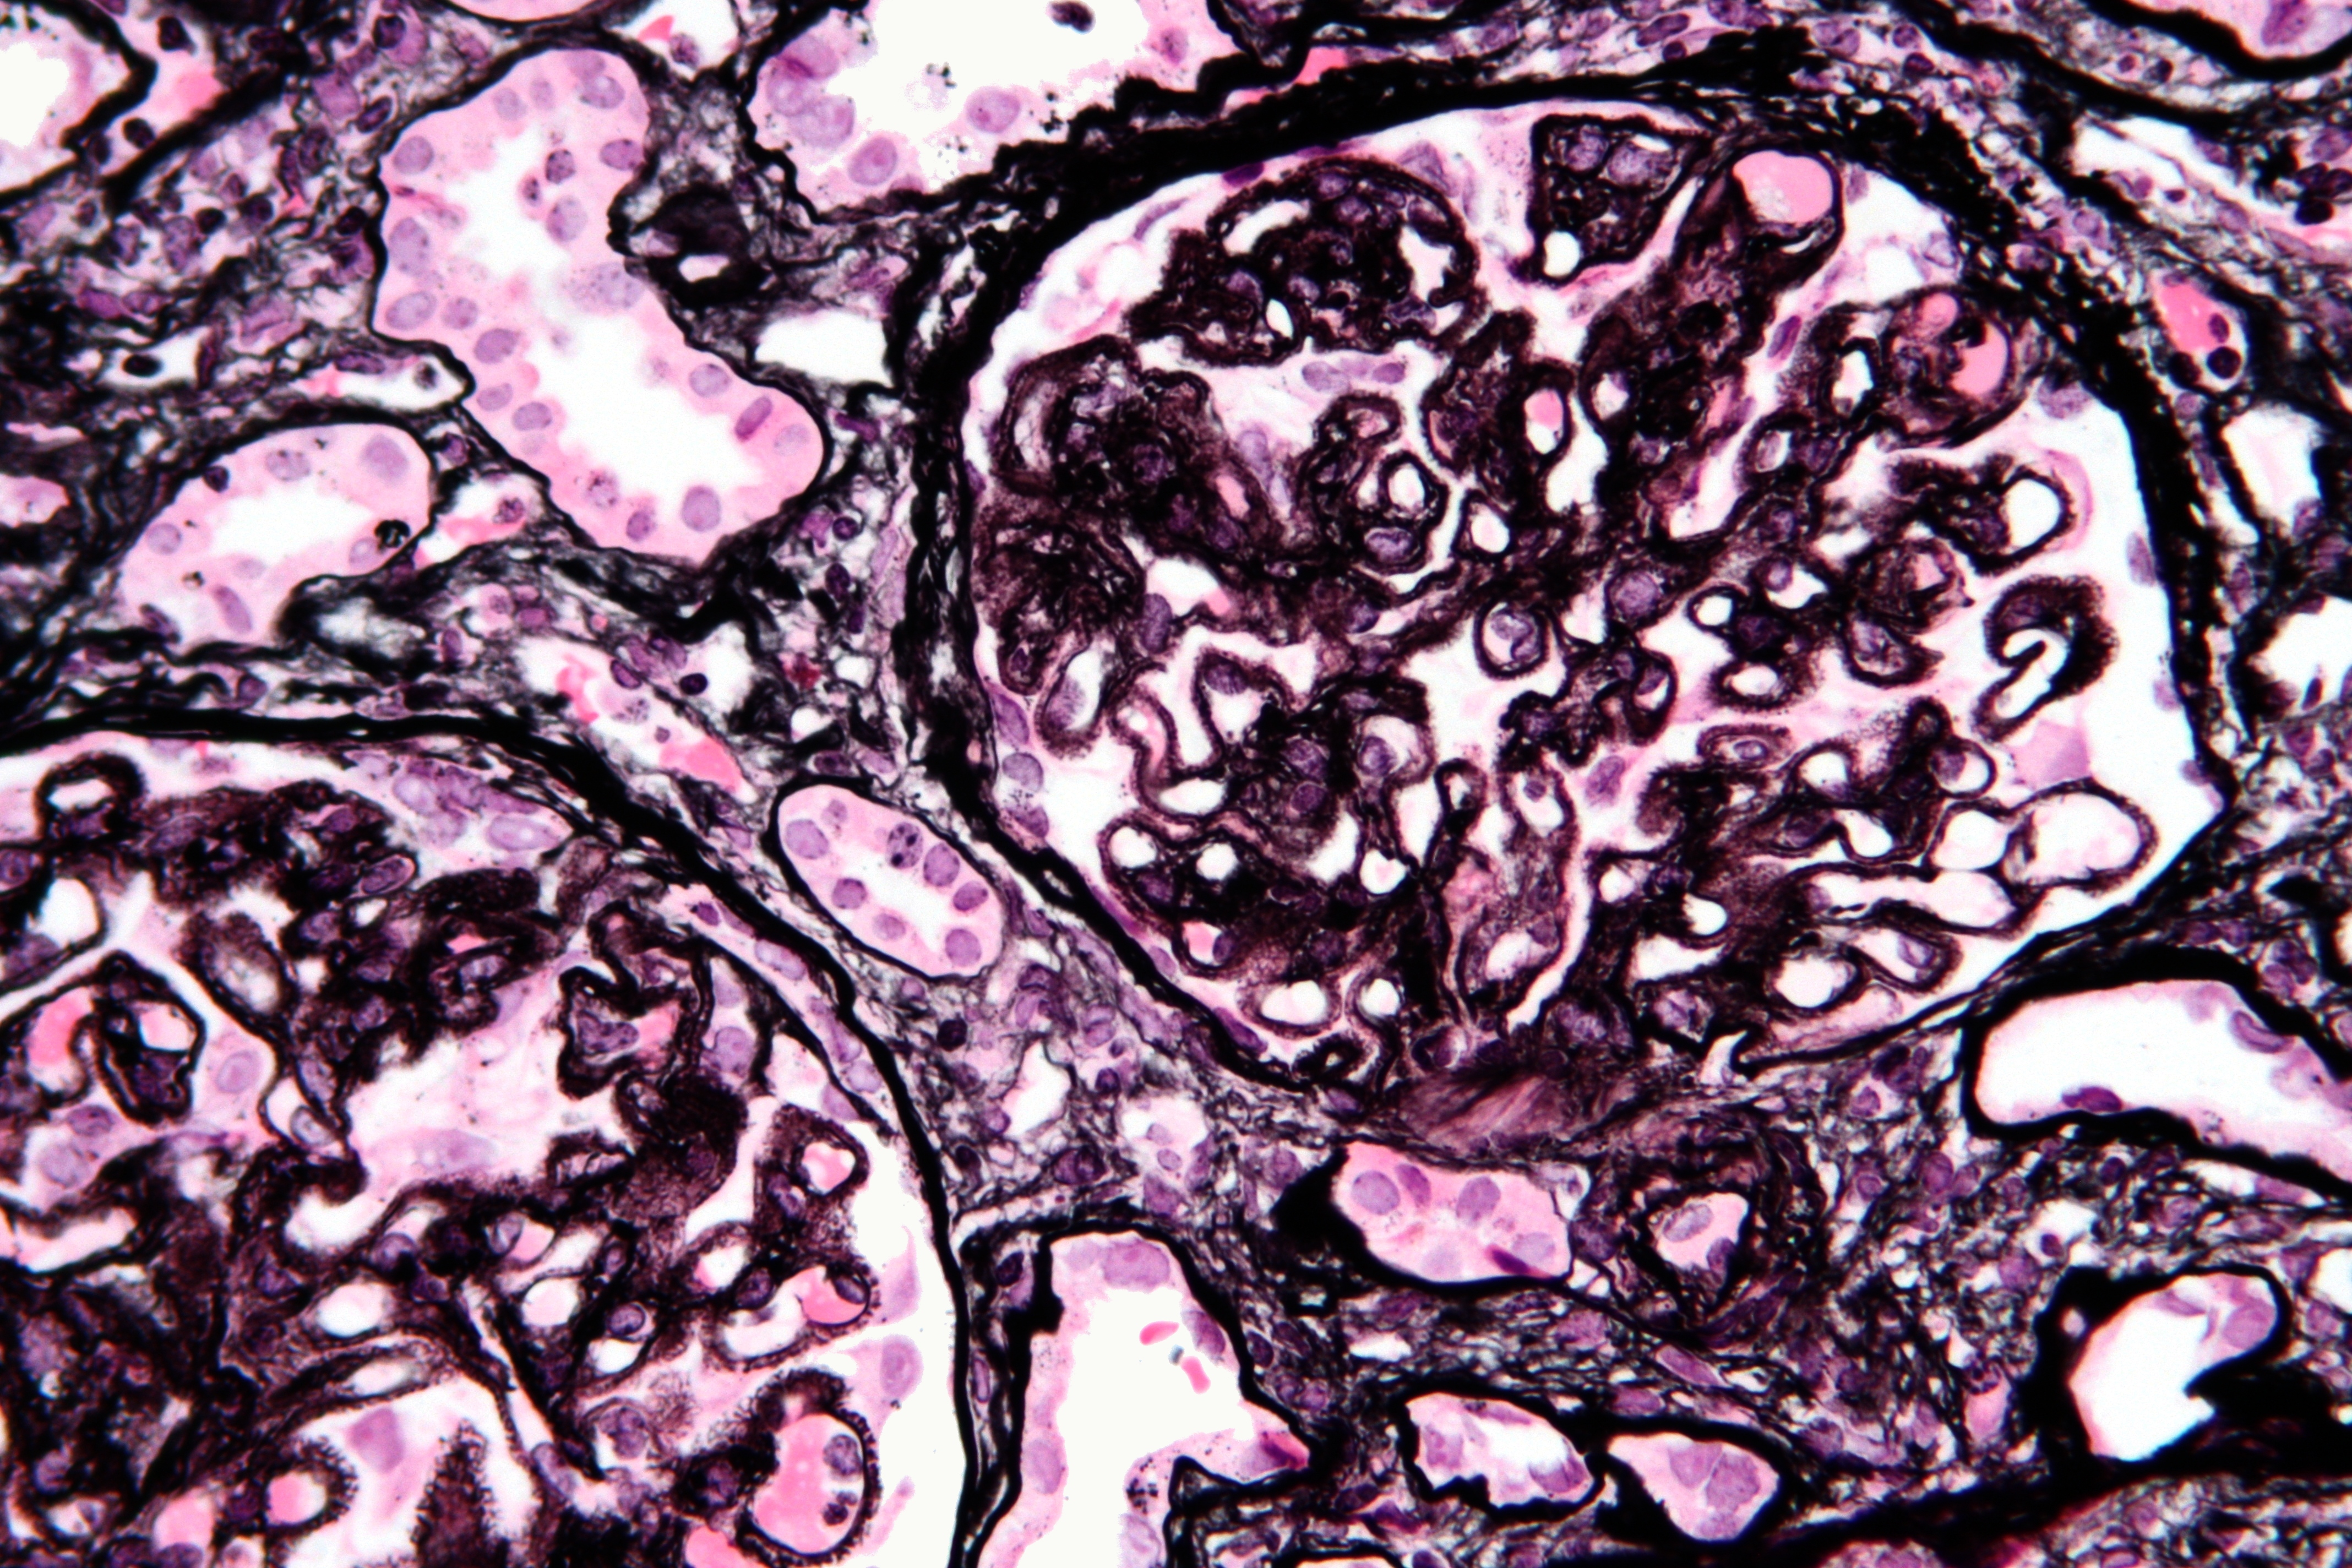

3.Métodos de imunofluorescência indireta e ELISA são  eficazes para a detecção dessa doença autoimune.

E, no caso da nefropatia membranosa primária, os antígenos PLA2R e THSD7A são amplamente reconhecidos como os principais alvos de autoanticorpos da doença. Por isso, a utilização de kits pelos métodos de imunofluorescência indireta e ELISA garantem uma maior acurácia e especificidade no diagnóstico. Além disso, o teste não é invasivo como a realização de biópsia, já que é realizado por meio de amostra de soro do paciente.

O primeiro deles é justamente a THSD7A (trombospondina tipo 1 com domínio contendo 7A) e o outro é o PLA2R (receptor de fosfolipase A2), que também é uma glicoproteína expressa nas superfícies dos s podócitos. Ambos podem ser investigados por meio de testes sorológicos, através das técnicas de ELISA e imunofluorescência indireta. O kit anti-THSD7A é elaborado com a tecnologia exclusiva do BIOCHIP da EUROIMMUN, sendo um suplemento ideal ao Anti-receptor de Fosfolipase A2 (PLA2R) para classificação sorológica de casos suspeitos de nefropatia membranosa primária (NMp).

O novo kit de imunofluorescência indireta da EUROIMMUN — anti-THSD7A — é um teste CBA (cell based assay)  baseado em células transfectadas, ou seja, células humanas que tiveram a inserção da sequência de DNA específica codificante para essa proteína. Então, ao acrescentar a amostra do paciente na lâmina, apenas os autoanticorpos específicos contra THSD7A irão reagir com o substrato do BIOCHIP da lâmina. Isso significa uma especificidade de 100% e uma sensibilidade que atinge 94%.